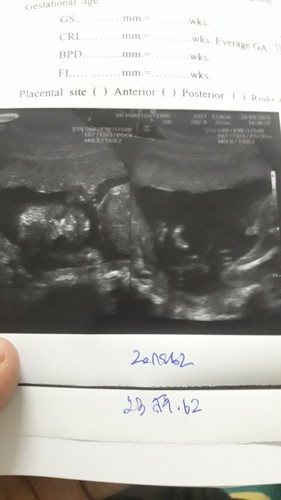

เดือนแล้วหมอบอก ผู้หญิง เดือนนี้จู๋โผล่ แม่ๆช่วยดูหน่อยคะ ว่าจู๋จริงๆใช่ไหม

บ้านนี้ซาวด์ครั้งแรกหมอบอก ช.70% ญ. 30% พอไปซาวด์รอบ2 หมอบอกผู้หญิง

ภาพไม่ค่อยชัดเลยค่ะ